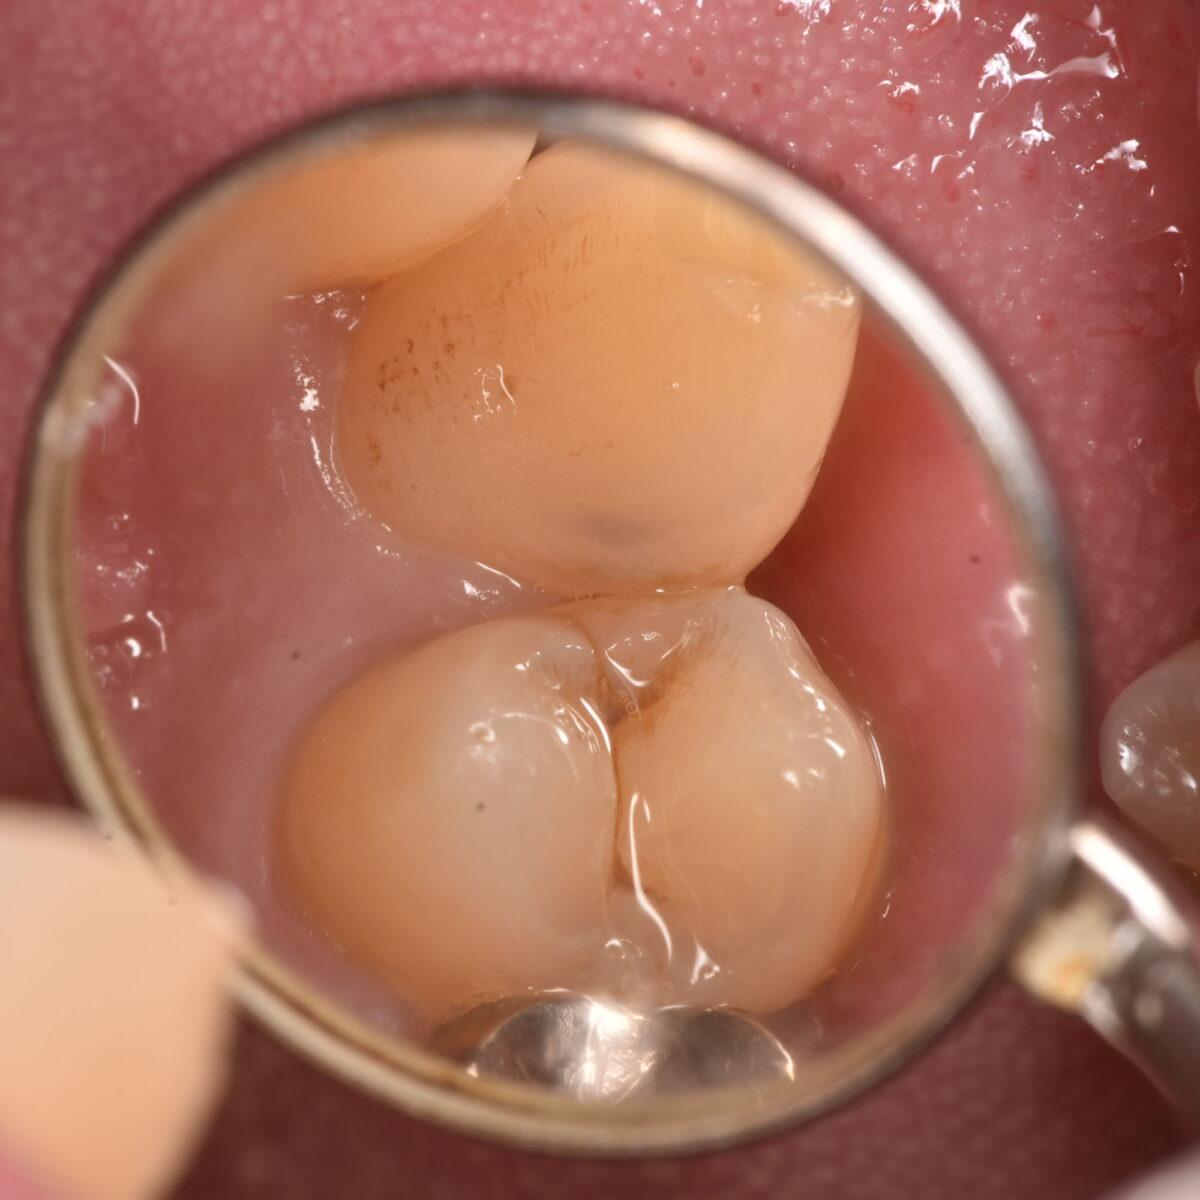

見た目には問題なく見えても、内部でむし歯が進行していたケース

症状のある・なしではわるくなっているかどうかの判定はできない 【東京メトロ東西線妙典駅 徒歩5分の歯医者】市川、妙典の歯科医院、めぐりデンタルクリニックの梶原です。 「むし歯の痛み…